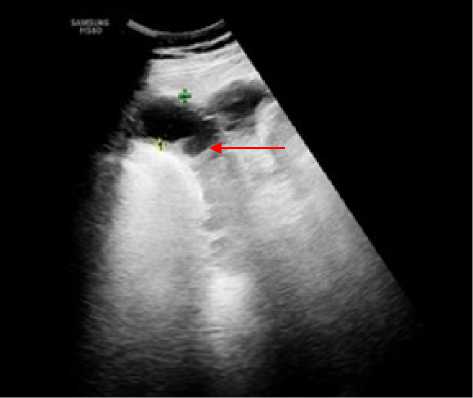

Всего в 12 случаях из 25 в разные сроки (7–21 сутки) с момента поступления в стационар имелись изменения в стенках толстой кишки в виде утолщения стенок различных отделов толстой кишки, чаще всего, сигмовидной и слепой, что выражалось в утолщении стенок до 7–10 мм, структура стенки пониженной эхогенности с инфильтрацией подслизистого слоя повышенной эхогенности, просвет кишки был сужен. В режиме ЦДК получить артериальный спектр не удалось. Выявленные изменения стенок толстой кишки были расценены как воспалительные на фоне деструктивных изменений забрюшинной клетчатки (рис. 4).

Рисунок 4. Эхограмма фрагмента толстой кишки с утолщенными стенками ( А ) на фоне деструктивных изменений клетчатки параколон ( Б )

Figure 4. Echogram of a fragment of the colon with thickened walls ( A ) against the background of destructive changes in the paracolonic tissue ( Б )